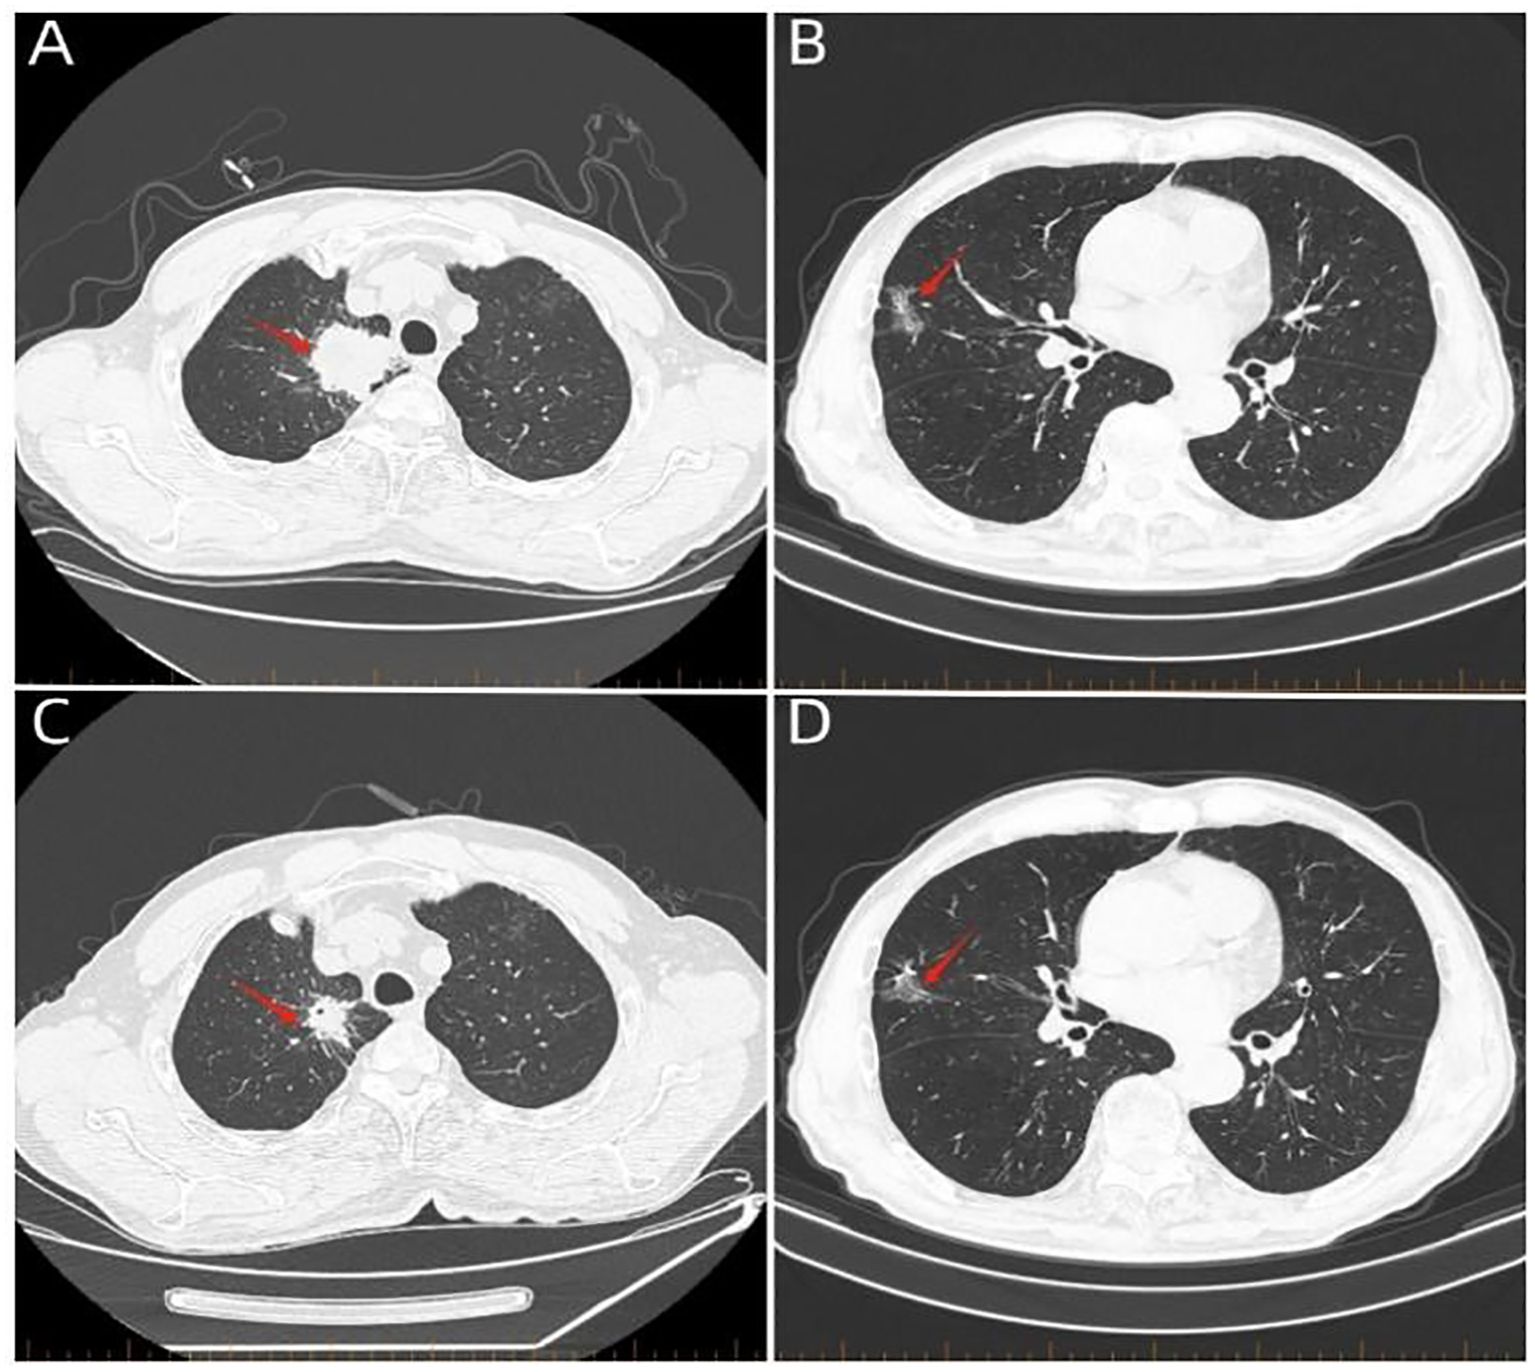

Figure 2

Four-panel image of CT scans showing lung cross-sections. Panel A and C highlight a nodule in the left lung with a red arrow, indicating a specific area of interest. Panels B and D depict a similar area in a different lung section, also marked with a red arrow.

Figure 2. Whole-body computed tomography scan. (A) Computed tomography scan on March 16, 2023, showing a 6.4-cm × 4.7-cm mass in the apical segment of the right upper lobe of the lung (red arrow). (B) Computed tomography scan on March 16, 2023, showing a mass in the middle lobe of the right lung (red arrow). (C) Computed tomography scan on June 6, 2023, showing a 3.1-cm × 2.4-cm mass in the apical segment of the right upper lung (red arrow). (D) Computed tomography scan on June 6, 2023, showing the middle lobe of the right lung with an occupancy (red arrow). A 3.1-cm × 2.4-cm mass is seen in the apical segment (red arrow).

A 74-year-old male patient presented with cough and sputum with intermittent blood in the sputum without obvious triggers. He was seen in a local hospital, where a computed tomography (CT) examination showed a right upper lobe lung mass, which was left untreated. He was seen in the Department of Thoracic Surgery of Xinhua Hospital, affiliated with Dalian University, on March 15, 2023, where he was treated with a biopsy of the cervical lymph nodes. The pathology showed metastatic adenocarcinoma (Figure 1A), and genetic testing found no mutations in EGFR, ALK, HER-2, ROS-1, RET, NTRK, BRAF, and MET. The following day, a chest CT was performed, which showed occupancy in the upper lobe (Figure 2A) and the middle lobe (Figure 2B) of the right lung. In addition, a 6.4-cm × 4.7-cm mass was seen in the apical segment of the upper lobe of the right lung, within which speckled calcification was observed, with an irregular margin and short burrs. The enhanced scan showed an uneven and obvious enhancement of the lesion, which was closely related to the adjacent pleura with an unclear demarcation (Figure 2A), and occupancy in the middle lobe of the right lung. Chemotherapy with pemetrexed + carboplatin + bevacizumab was administered for four cycles. A follow-up chest CT on June 6, 2023, showed a 3.1-cm × 2.4-cm mass in the right upper apical segment of the lung (which was significantly reduced compared with that observed on March 15, 2023) (Figure 2C), and the lesion in the middle lobe of the right lung was roughly similar to the previous one (Figure 2D). The patient’s symptoms such as coughing, coughing up sputum, and coughing up blood were significantly relieved after the treatment, and he stopped the treatment on his own. In September 2023, the patient was admitted to our hospital due to progressive urinary difficulty, and the pathology was suggested: prostate cancer (Figure 1B). He was given bicalutamide and leuprolide for endocrine therapy. On January 8, 2024, prostate magnetic resonance imaging showed that the prostate gland was slightly enlarged, approximately 4.3 cm × 3.8 cm × 2.6 cm, and the prostate peritoneum was poorly illuminated. The prostate migratory zone showed multiple rounded masses, with the larger ones measuring approximately 1.8cm × 1.4 cm, presenting a low signal on T1-weighted imaging (T1WI) and a slightly high signal on T2-weighted imaging (T2WI), with a poorly demarcated central gland and peripheral zone. The peripheral zone was not clearly demarcated. The central gland and the peripheral band were not clearly demarcated. The peripheral band showed a mass shadow of approximately 1.6 cm in length at 5 o’clock, which broke through the peritoneum and had a slightly restricted diffusion. The border was not clear (Figures 3A–C). Pathology consultation of the prostate specimen was given, which was consistent with a diagnosis of PCa, supplemented with immunohistochemistry of the cervical lymph nodes, prostate-specific antigen (PSA) (part 3+) (Figure 1C), P504S (3+) (Figure 1D), TTF1 (−), CK7 (−), CK20 (−), napsin A (−), and P40 (−), consistent with metastatic carcinoma of the prostate. The patient was recommended to further undergo bronchoscopy or percutaneous lung puncture biopsy in order to clarify the pathologic diagnosis and treat the lung cancer according to the pathologic diagnosis. However, the patient had peripheral lung cancer, and the lung puncture biopsy had a high risk of pneumothorax due to the long puncture path. Moreover, the tumor tissue could not be retrieved by bronchoscopy. Therefore, the patient’s family members refused to accept lung puncture biopsy and bronchoscopy and gave up the further genetic testing and molecular targeting therapy. They also refused to accept tumor resection of the right upper lobe of the lung and demanded that chemotherapy and immunotherapy be selected for the chemotherapy regimen for the lung cancer. Considering that patients with PCa can survive for a long time but those with lung cancer have a short survival period, and due to the patient having developed a weaker breath sound in the right lung compared with the left lung, we chose docetaxel, which is an effective chemotherapeutic drug for both PCa and lung cancer, combined with the immunotherapy drug karelizumab. The patient started two cycles of docetaxel + karelizumab on January 10, 2024. The review after treatment showed that the lung lesions were reduced and the prostate lesions, the neck lymph nodes, and other metastatic lesions in the lung were all stable. As the lesion in the upper lobe of the right lung was considered to have a high probability of being a primary cancer of the lung, the treatment was therefore effective. All other lesions were considered to be metastases of PCa. It is worth noting that, in the course of chemotherapy, new bone metastatic lesions appeared, and the possibility of the bone metastases originating from PCa was considered to be high. The disease progression of the patient is shown in Figure 4.